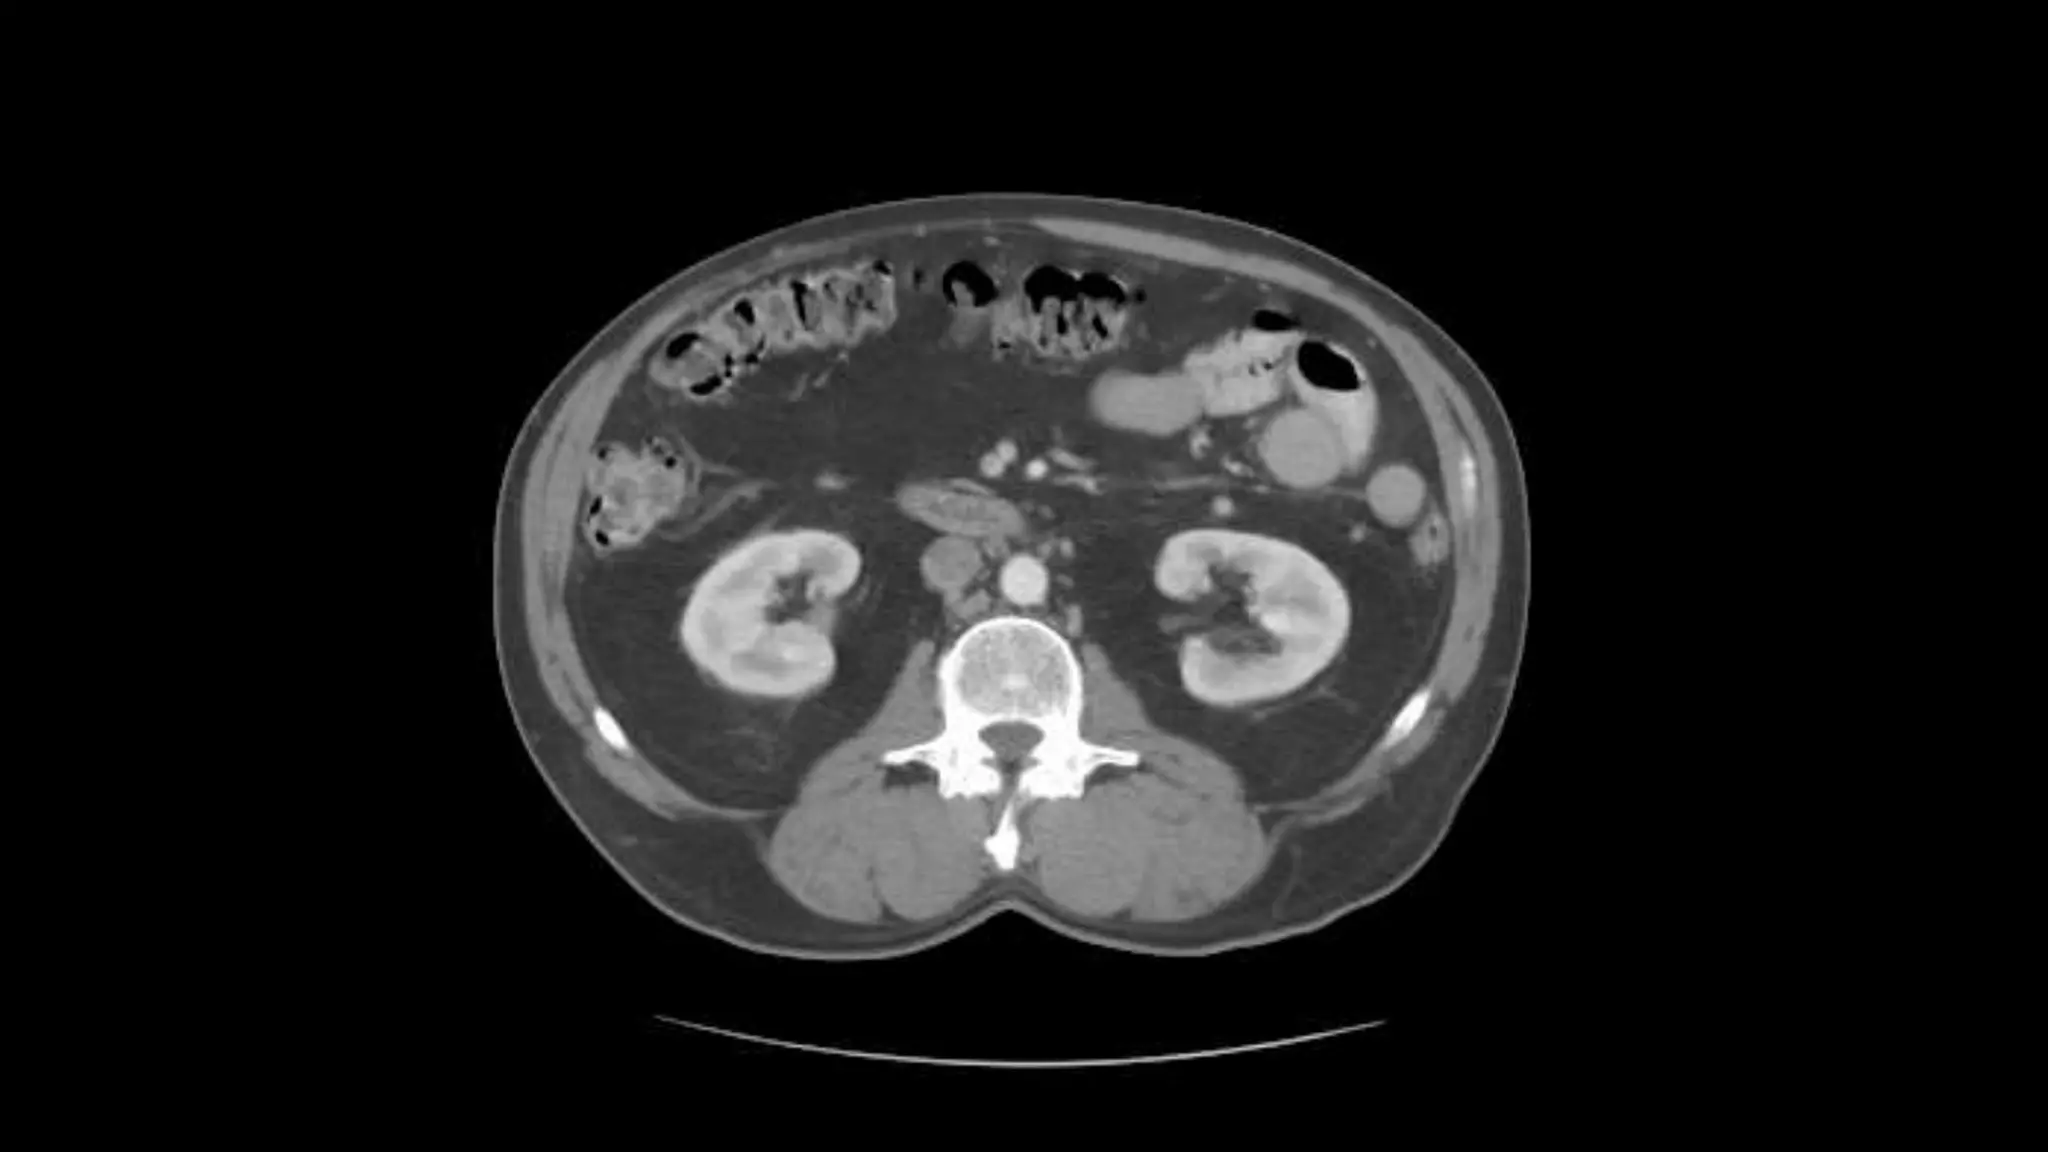

Rt. and Lt.Kidneys

Pancreas

Renal Veins emptying into the IVC. We also see the right renal artery branching

off the Aorta, follow it down till you see it enter the right kidney. The Superior

Mesenteric Vein is outlined on the top of this image. If you follow the SMV up, you

will see it empty into the Portal Vein.

Here we see the right and left renal vein entering into the Inferior Vena Cava. We

Also see the left renal artery branching off the aorta and heading toward the left

kidney. Page up and down to trace these vessels.

Superior Mesenteric Vein – follow it up as it joins the Splenic

Vein to form the Portal Vein